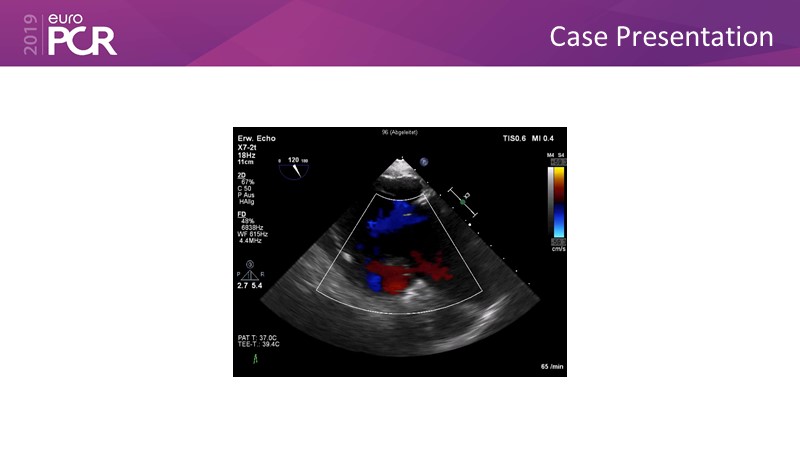

Addressing tricuspid regurgitation with annular reduction: the Cardioband tricuspid system

Consult this session to understand how patients with tricuspid regurgitation and annular dilatation can benefit from Cardioband system...

- To understand how patients with tricuspid regurgitation and annular dilatation can benefit from Cardioband system

- To learn how to perform a good echo workup for Cardioband tricuspid system